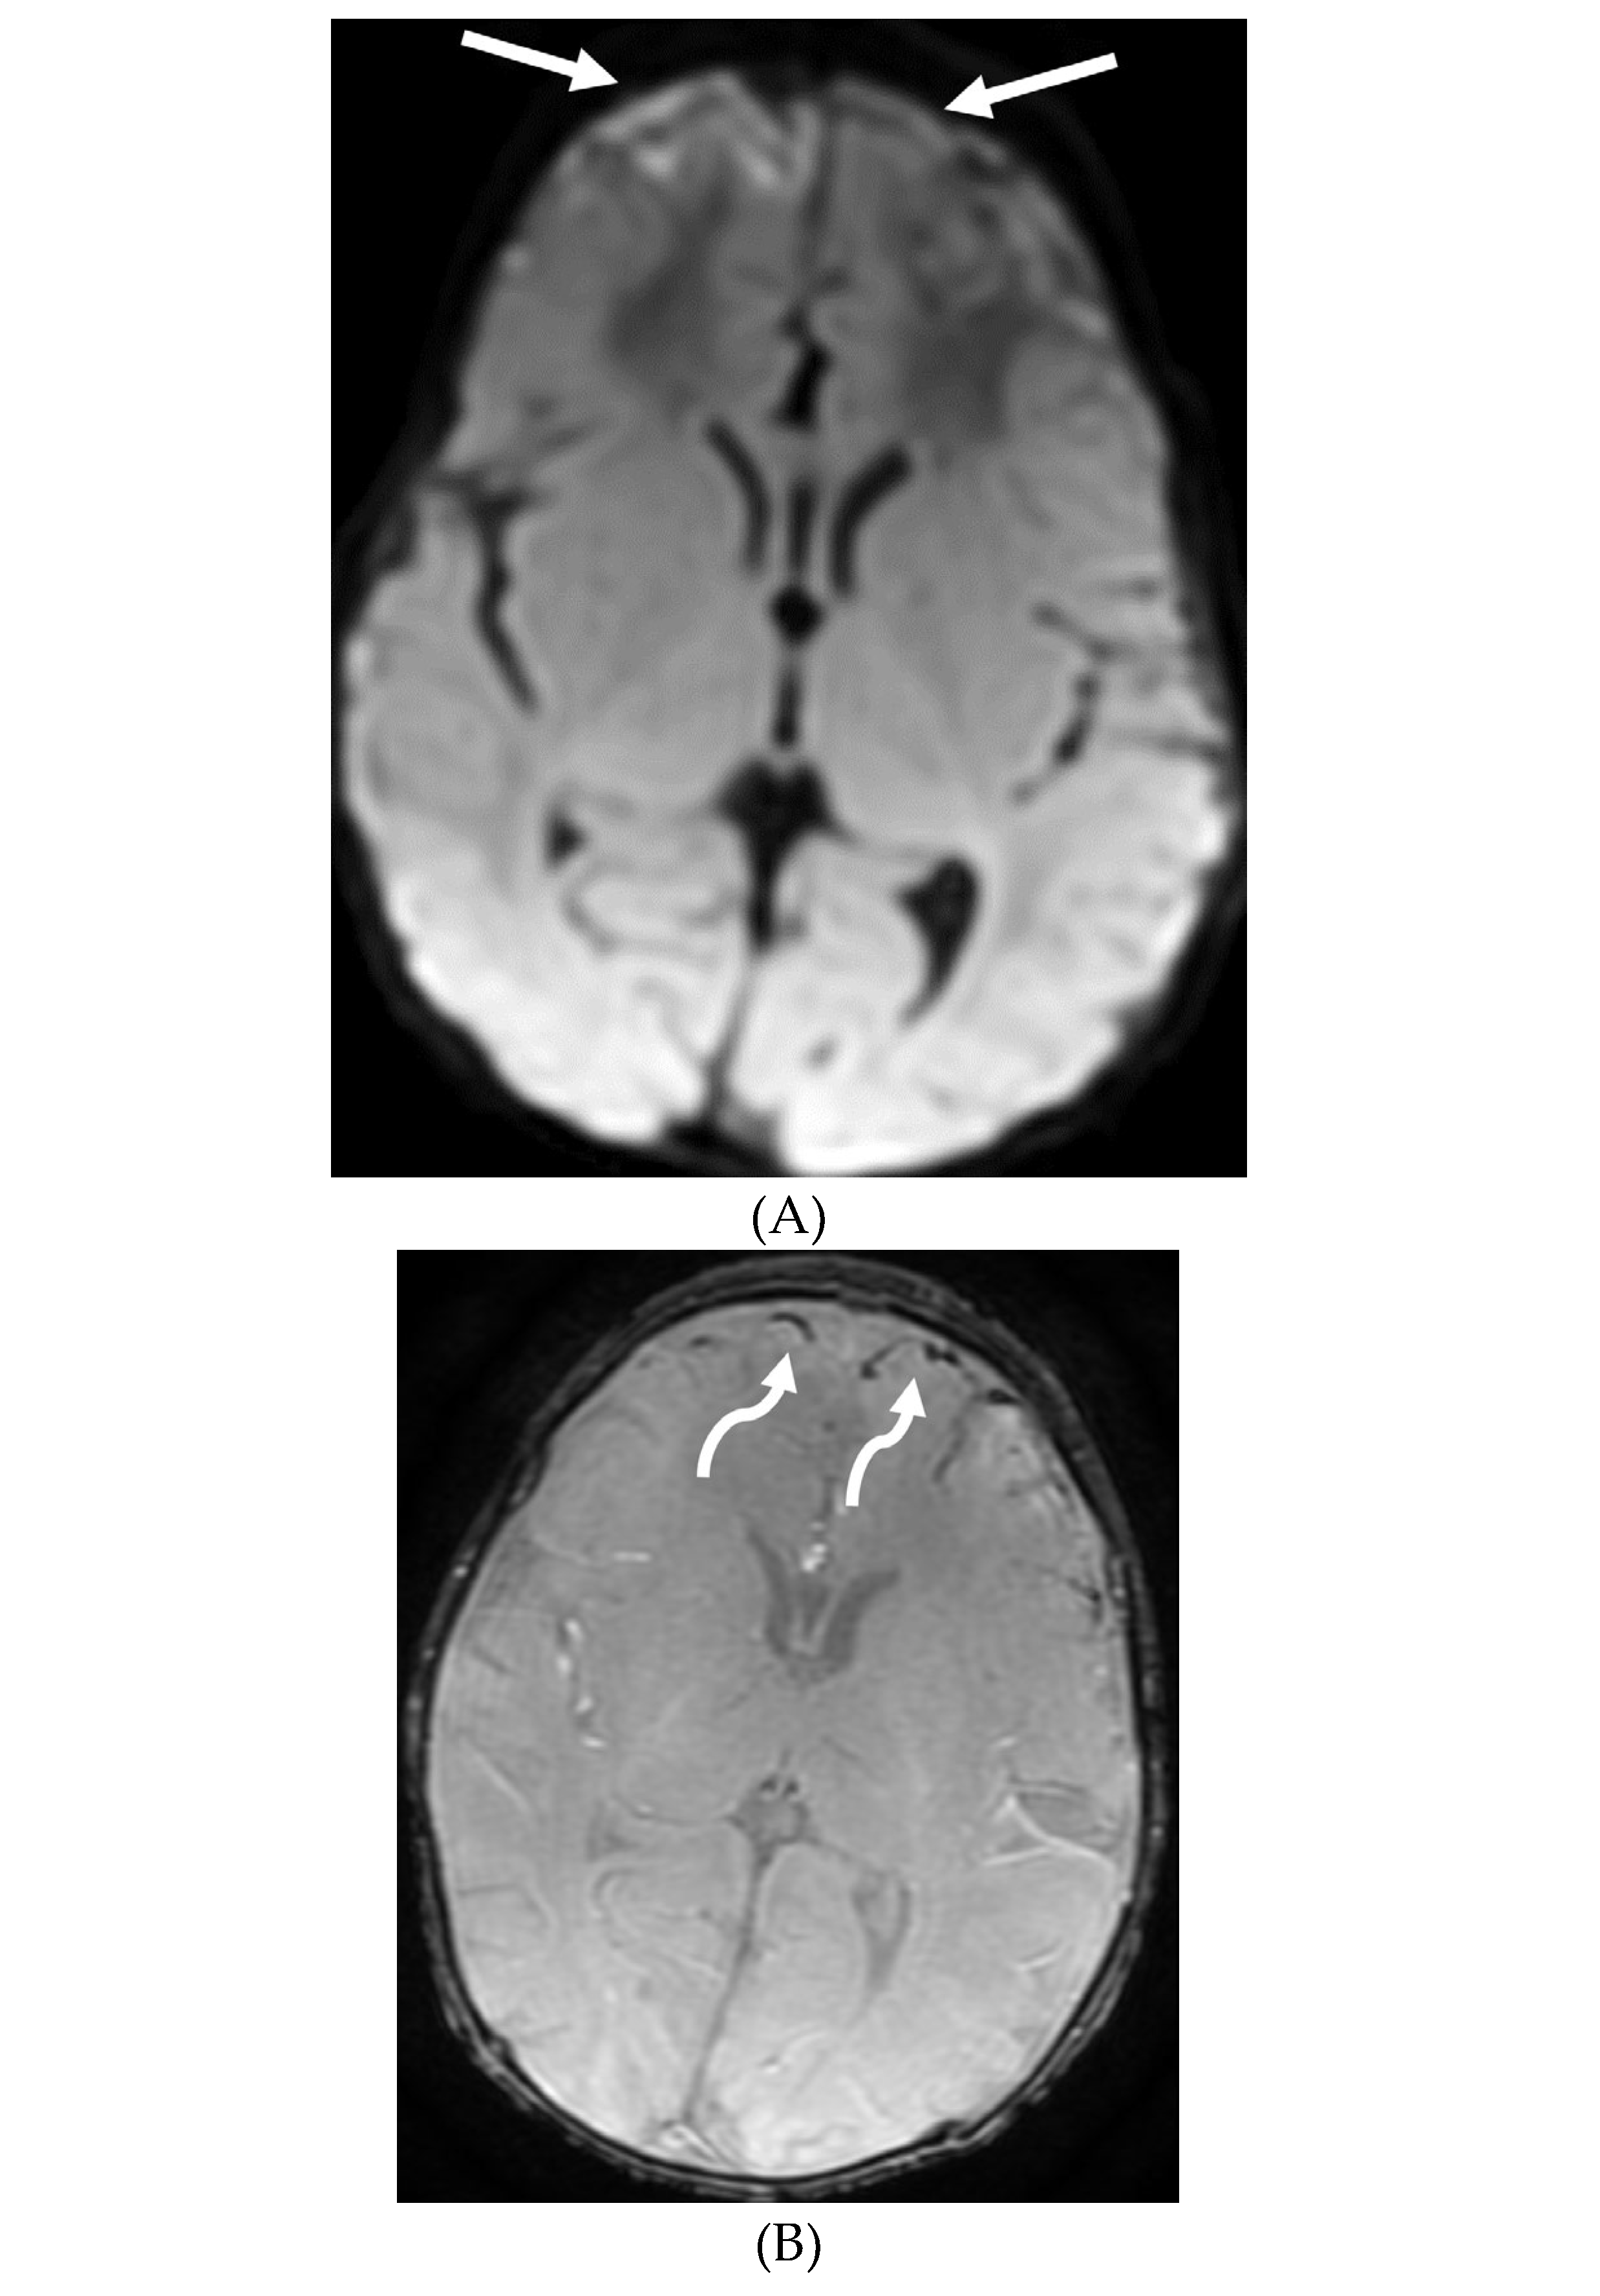

GUILLAIN BARRE SYNDROME

- Alkan O, Yildirim T, Tokmak N, Tan M. Spinal MRI findings of guillain-barré syndrome. J Radiol Case Rep. 2009;3(3):25-8. Epub 2009 Mar 1. PMID: 22470650; PMCID: PMC3303301. [CrossRef]

- Zuccoli G, Panigrahy A, Bailey A, Fitz C. Redefining the Guillain-Barré spectrum in children: neuroimaging findings of cranial nerve involvement. AJNR Am J Neuroradiol. 2011 Apr;32(4):639-42. Epub 2011 Feb 3. PMID: 21292802; PMCID: PMC7965877. [CrossRef]

- Yikilmaz A, Doganay S, Gumus H, Per H, Kumandas S, Coskun A. Magnetic resonance imaging of childhood Guillain-Barre syndrome. Childs Nerv Syst. 2010 Aug;26(8):1103-8. Epub 2010 Jun 17. PMID: 20556395. [CrossRef]

- Byun WM, Park WK, Park BH, Ahn SH, Hwang MS, Chang JC. Guillain-Barré syndrome: MR imaging findings of the spine in eight patients. Radiology. 1998 Jul;208(1):137-41. PMID: 9646804. [CrossRef]